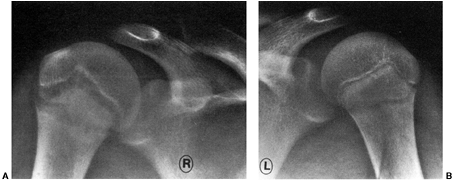

holes and avoid any hardware crossing the physis (Fig. 32.17). Advantages of this technique are improved graft fixation and graft isometry (152). Excellent results are reported in adolescents close to maturity (152) (Fig. 32.18 A,B). Variations of this technique include the use of Achilles tendon or patellar tendon allograft (154).

children with 1 year or less of growth remaining as determined by a

wrist x-rays and the Greulich and Pyle atlas (Fig. 32.19 A,B).

Figure 32.18 A:

Anteroposterior radiograph of skeletally immature child who underwent transphyseal anterior cruciate ligament reconstruction utilizing autogenous hamstring tendon. Note vertical orientation of drill holes in proximal tibia and distal femur. B: Lateral radiograph of same patient. |

![]() |

|

Figure 32.19 A: Magnetic resonance imaging (MRI) (axial) showing small, centrally placed drill hole in proximal tibia (white arrow). B:

Lateral MRI image of same patient showing graft filling tibial tunnel. Note growth arrest lines on distal femur proximal to distal femoral physis (white arrows) indicating continued growth. |